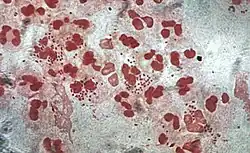

| |

| Gonococcal lesion on the skin | |